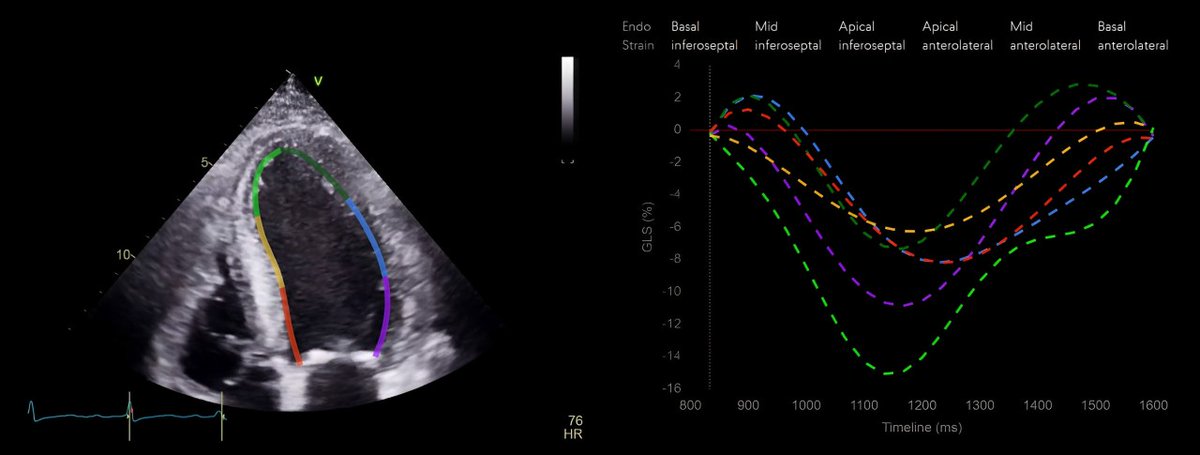

Us2 (@us2_ai) 's Twitter Profile Photo

FDA clearance for Us2.v2, featuring 45 automated echo parameters, including strain analysis, marking a significant stride in medical innovation! us2.ai/us2-ai-receive…

FDA clearance for Us2.v2, featuring 45 automated echo parameters, including strain analysis, marking a significant stride in medical innovation!

us2.ai/us2-ai-receive…